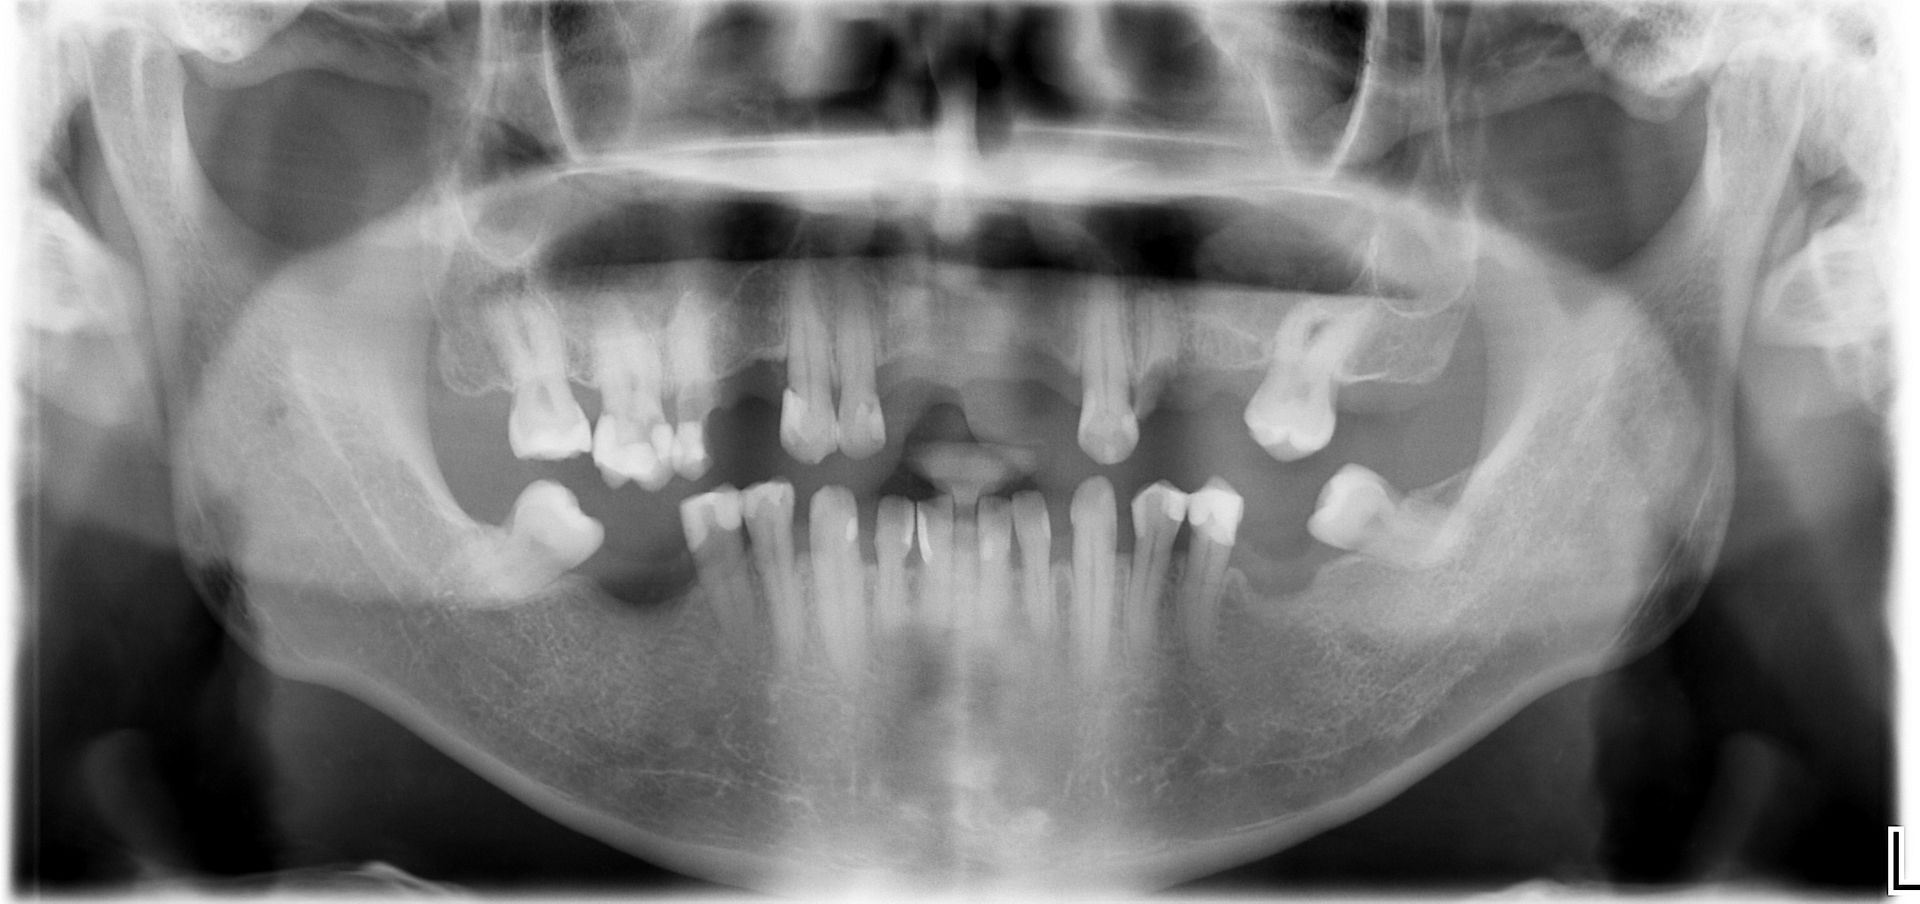

The American Academy of Implant Dentistry recognizes Dr. Krasne as an Associate Fellow in Implant Dentistry because of his expertise in implant dentistry surgical and restorative procedures. Dr. Krasne dedicated hundreds of hours and spent tens of thousands of dollars on training and state-of-the-art equipment to develop a practice that delivers superior implant results to patients. Dr. Krasne completed his AAID Maxicourse training at the Dental College of Georgia in Augusta and passed both written and oral boards from the AAID. Dr. Krasne completed his education through Advanced Operative Dentistry and Advanced Oral Surgery, California Implant Institute Live Surgical Fellowship, and the Zest Dental Mastership for Snap-on Dentures and Advanced Implant Planning. Parkway Restorative Dentistry has acquired state-of-the-art technology, including CBCT imaging, 3-D dental imaging, 3-D printing, and In-house mill and design components, which work together to achieve perfect patient outcomes. During your consultation with Dr. Krasne you can trust that he will work to discover a solution that meets your requirements and financial situation.